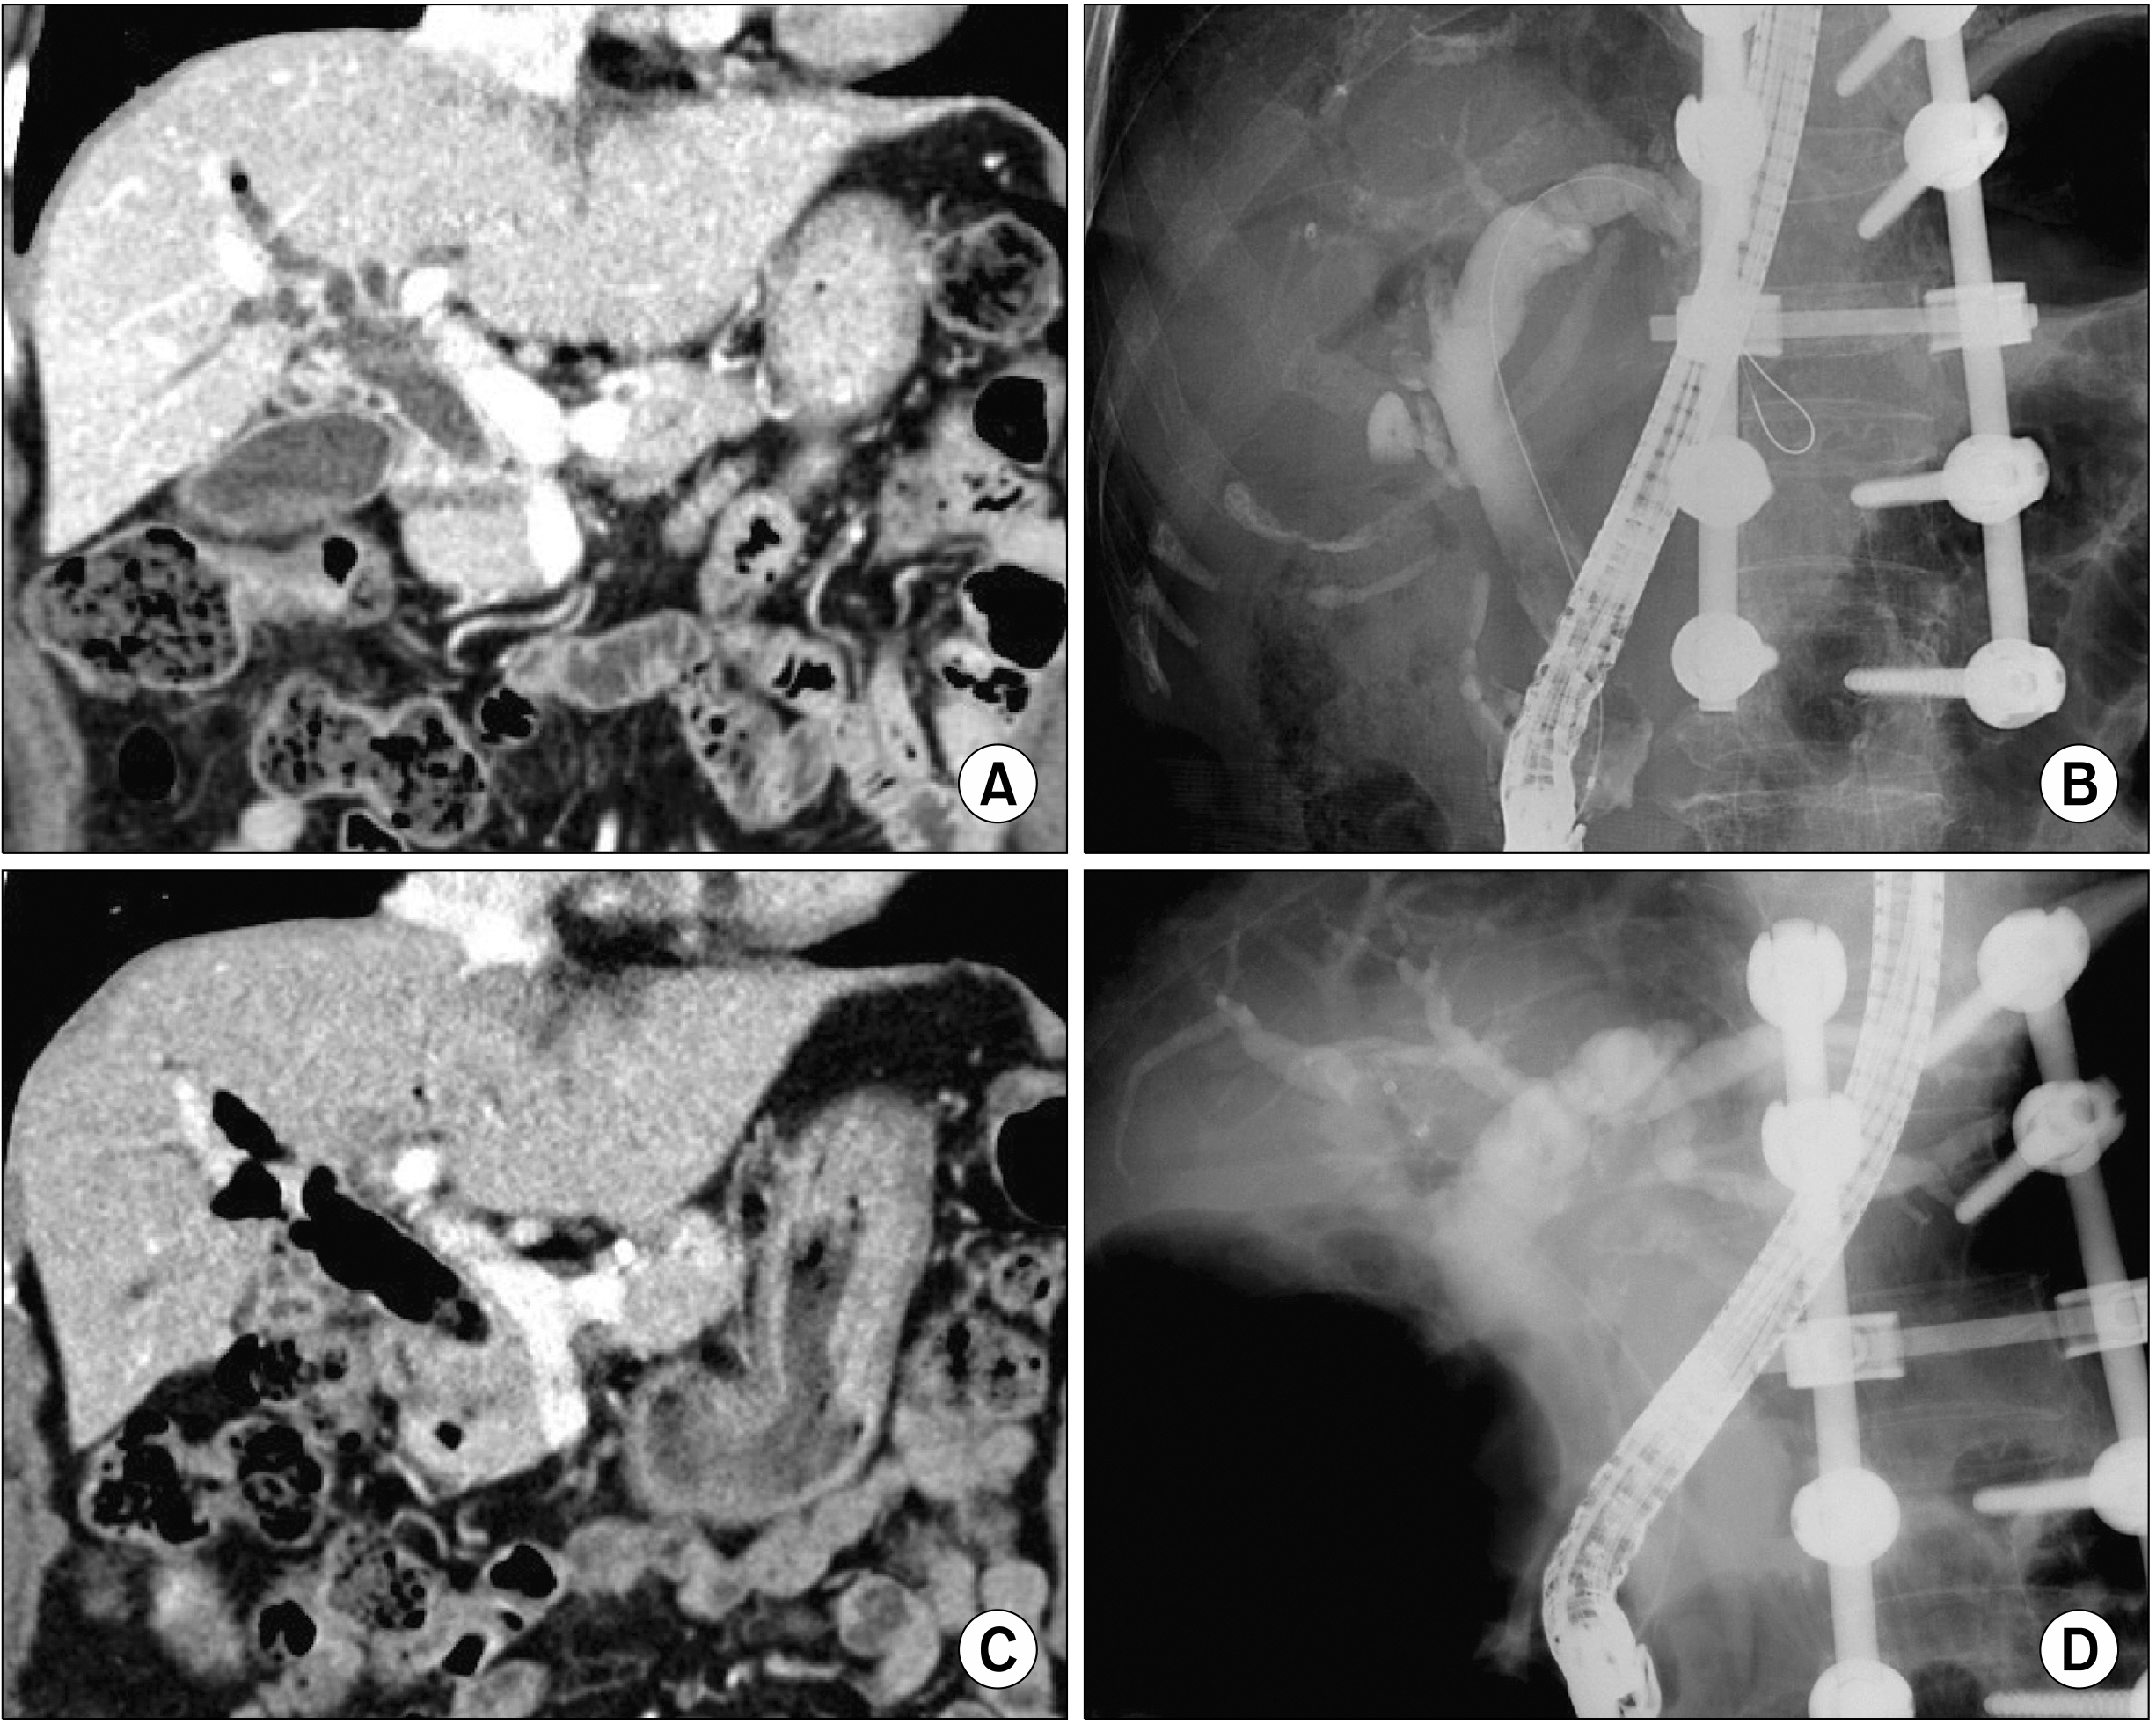

- Despite development in endoscopic treatment and minimally invasive surgery for choledocholithiasis, there remains a small number of patients who require bypass Roux-en-Y choledochojejunostomy (RYCJ) because of the intractable occurrence of common bile duct (CBD) stones. We herein present the detailed procedures of open RYCJ customized for intractable choledocholithiasis. The first method is a side-to-end choledochojejunostomy with intraluminal closure of the distal CBD. This method was applied to a 79-year-old female patient who underwent endoscopic retrograde cholangiopancreatography (ERCP) more than 10 times in the past 14 years (Case No. 1). The distal CBD was explored through choledochotomy and then the distal CBD lumen was occluded with internal running sutures. A large-sized choledochojejunostomy was performed. The patient recovered uneventfully and has been doing well for the past 2 years. The second method is an end-to-end choledochojejunostomy with segmental CBD resection. It was applied to a 75-year-old male patient who underwent ERCP 9 times in the past 10 years (Case No. 2). The CBD was resected segmentally and a large-sized choledochojejunostomy was performed. The patient also recovered uneventfully and has been doing well for the past 2 years. In conclusion, the primary indication of bypass RYCJ is intractable choledocholithiasis which requires numerous sessions of endoscopic stone removal over a long period. Open RYCJ is the preferred procedure to date. If the papilla is patulous, the distal CBD should be occluded or resected to prevent reflux ascending cholangitis. We recommend to resect the intrapancreatic distal CBD if it is markedly dilated like choledochal cyst.